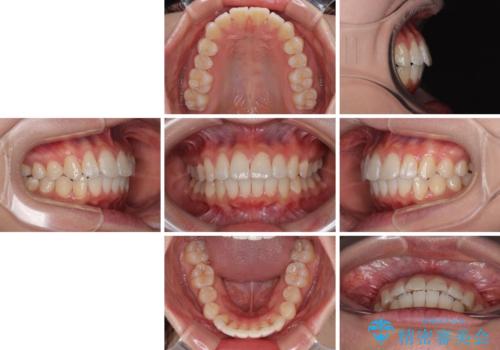

深い咬み合わせによる隙間 インビザライン矯正でコンプレックスを改善

インビザラインにより、上下の歯列を側方に拡大しつつ、前歯の隙間を閉じていくこととしました。

隙間の原因は強い咬合力や舌の突出癖、小帯の異常付着などがありますが、舌のトレーニングをしっかりと行いながら、装着時間を遵守して装着していただいたおかげで、スムーズに治療を終えることができました。